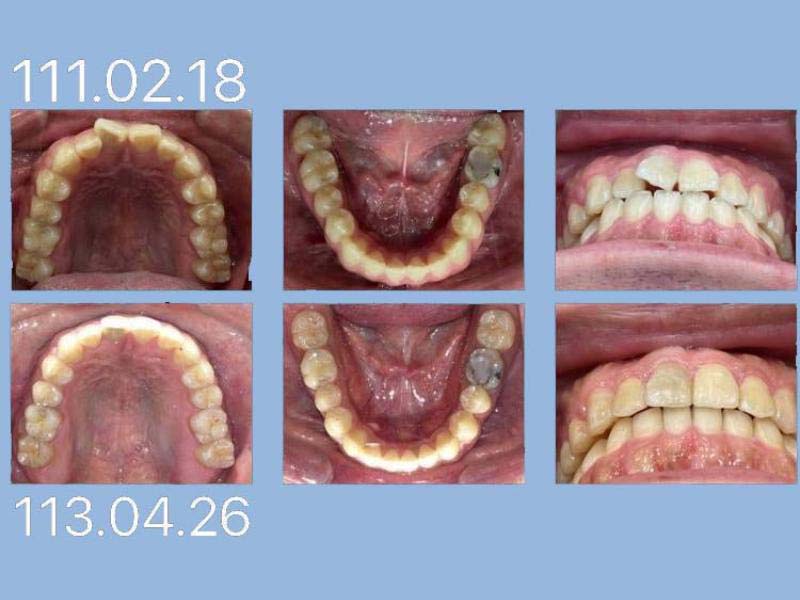

蕭先生 (22歲) 矯正完成

狀態:亂、擠、錯咬、牙周病、沒拔牙